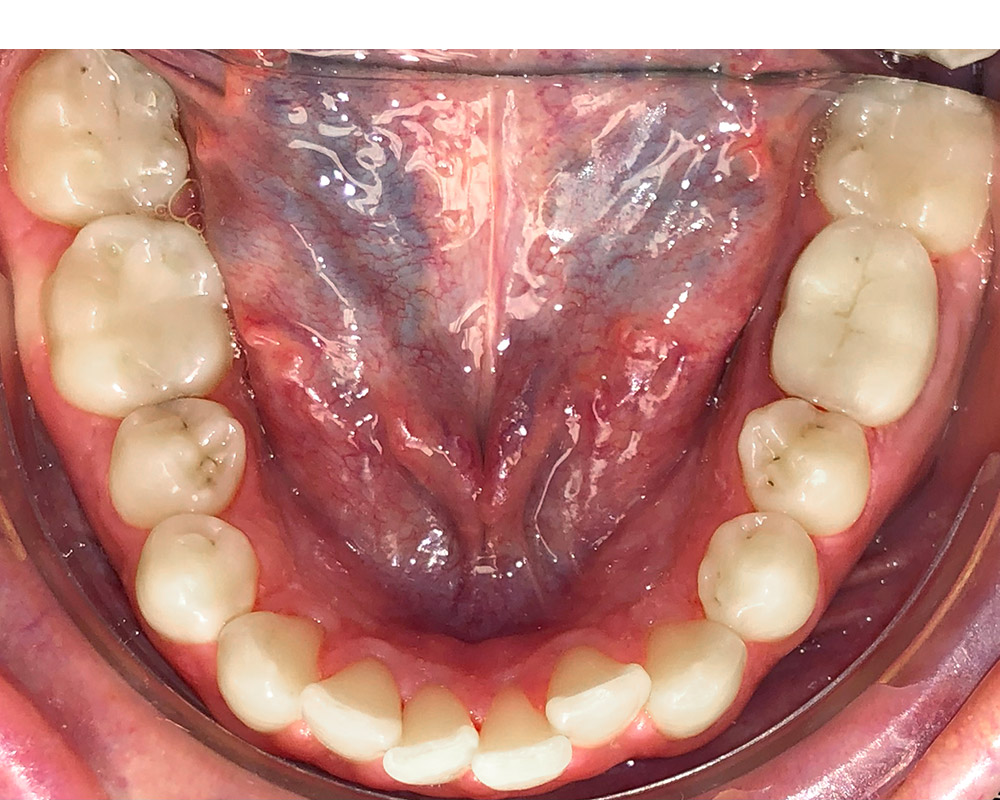

Кейс 11

Акинфиева Анна Владимировна

Количество кап ВЧ 12

Количество кап НЧ 16

ДО

ПОСЛЕ